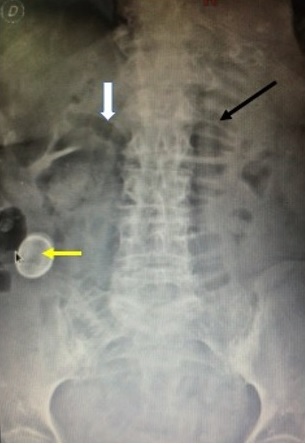

He was admitted to the Emergency Department with a clinical picture of intestinal occlusion. A simple abdominal radiograph was requested (only obtained in decubitus), observing the presence of Rigler's radiological triad, pathognomonic of the biliary ileum.

The 3 elements are indicated: dilated thin handles (black arrow), aerobilia (white arrow) and the ectopic calcified stone in the right iliac fossa (yellow arrow).

Gallstone ileus is intestinal occlusion as a consequence of the migration of a gallstone through a bilio-digestive fistula and its impaction, frequently at the level of the ileo-cecal valve. Usually it is a cholecysto-duodenal fistula, although it can also be a cholecysto-colonic fistula.

The classically described clinical picture is that of intermittent occlusion, being more frequent in elderly patients, with a long history of symptomatic biliary lithiasis.